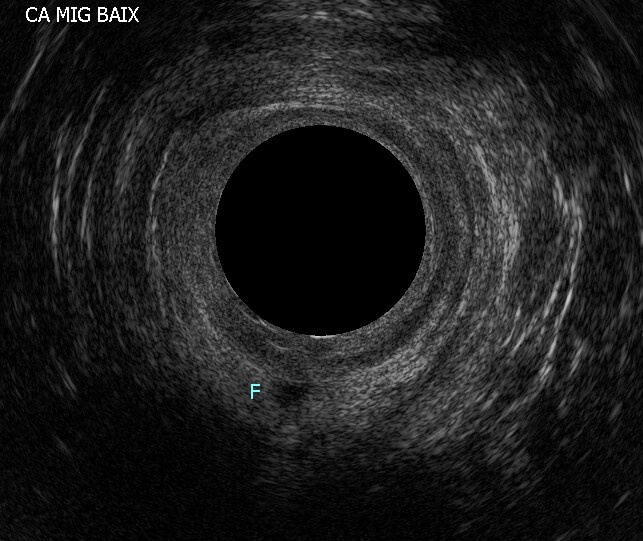

꼬리뼈 농양은 항문 주위에 감염된 "구멍"이나 개구부가 있는 질환으로 치루와 감별이 필요하다.[1]대부분 문진, 항문 내 촉진, 항문경을 이용한 관찰만으로 진단이 가능하다. 원발성 병소(농의 발생 원인) 및 누공의 상태를 자세히 확인하기 위해 초음파 검사를 이용한 항문 에코 검사나 자기공명영상(MRI) 검사 등이 필요한 경우가 있다.[1]

1차 진찰에서 누공 형성이 확실히 확인되면 항문 주위에 열린 누공 부위에 탐침(존데)이라고 불리는 금속 막대를 삽입하여 누공의 경로를 검사하기도 한다. 하지만 누공 형성이 충분하지 않은 경우 심한 고통을 수반하므로 탐침 검사는 충분한 마취하에 수술 중에 시행되는 경우가 많다.[1]

검사에서 누공의 형태나 일차 개구부의 위치를 알 수 없는 경우 수술이 불가능해져 정기적으로 절개 및 배농을 해야 할 수도 있지만, 항문 에코 검사나 MRI 검사 등 진단 기술의 향상으로 이러한 경우는 비교적 드물어지고 있다. 그러나 크론병이나 궤양성 대장염 등을 원인으로 발생한 치루의 경우, 원인 질환이 완전히 회복되지 않으면 언제든지 재발할 위험이 있으므로 수술 적응이 되지 않는 경우도 있다.[1]